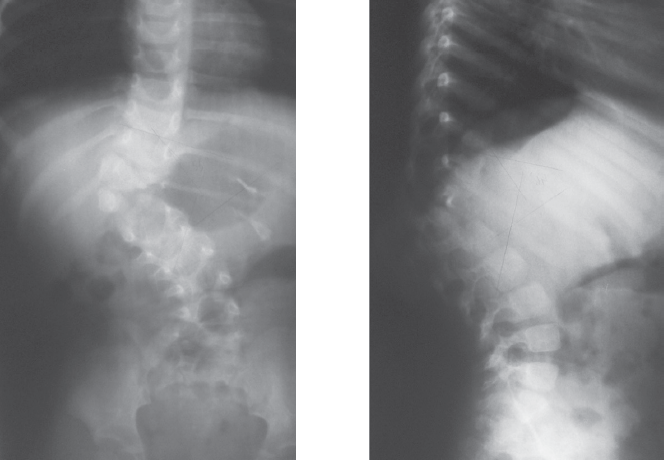

Наложено краниофеморальное скелетное вытяжение. За 35 суток достигнута коррекция сколиотической деформации на 17° (32 %), кифотической — на 12° (14 %). Учитывая расположение правого мочеточника в зоне доступа к телам позвонков грудопоясничного перехода, непосредственно перед основным этапом оперативного лечения под контролем флюороскопии в мочеточник заведен стент. В положении на левом боку выполнена торакофренолюмботомия через ложе 12-го ребра. Отмечено снижение высоты межпозвонковых дисков, отсутствие пульпозных ядер на вершине деформации, конкресценция тел Th12 и полупозвонка L1. Дискэпифизэктомия в парах Th11-Th12, L1-L2, L2-L3, спондилодез сульфатом кальция в комбинации с аутогенной костью (резецированное ребро). Между телами позвонков Th11 и L3 установлен сетчатый имплант Mash. Через тела позвонков Th11 и L3 бикортикально проведены винты, коммутированы стержнем. Плевральная полость и забрюшинное пространство дренированы. Рана послойно ушита. На 12-е сутки после операции больная вертикализирована в корсете. Через 5 месяцев госпитализирована для контрольного обследования и проведения заключительного этапа хирургического лечения. По данным рентгенографии, достигнутая коррекция сохраняется (рис. 5). В качестве заключительной операции выполнен задний спондилодез на вершине деформации.

Рис. 5. Рентгенограммы через 5 месяцев после операции